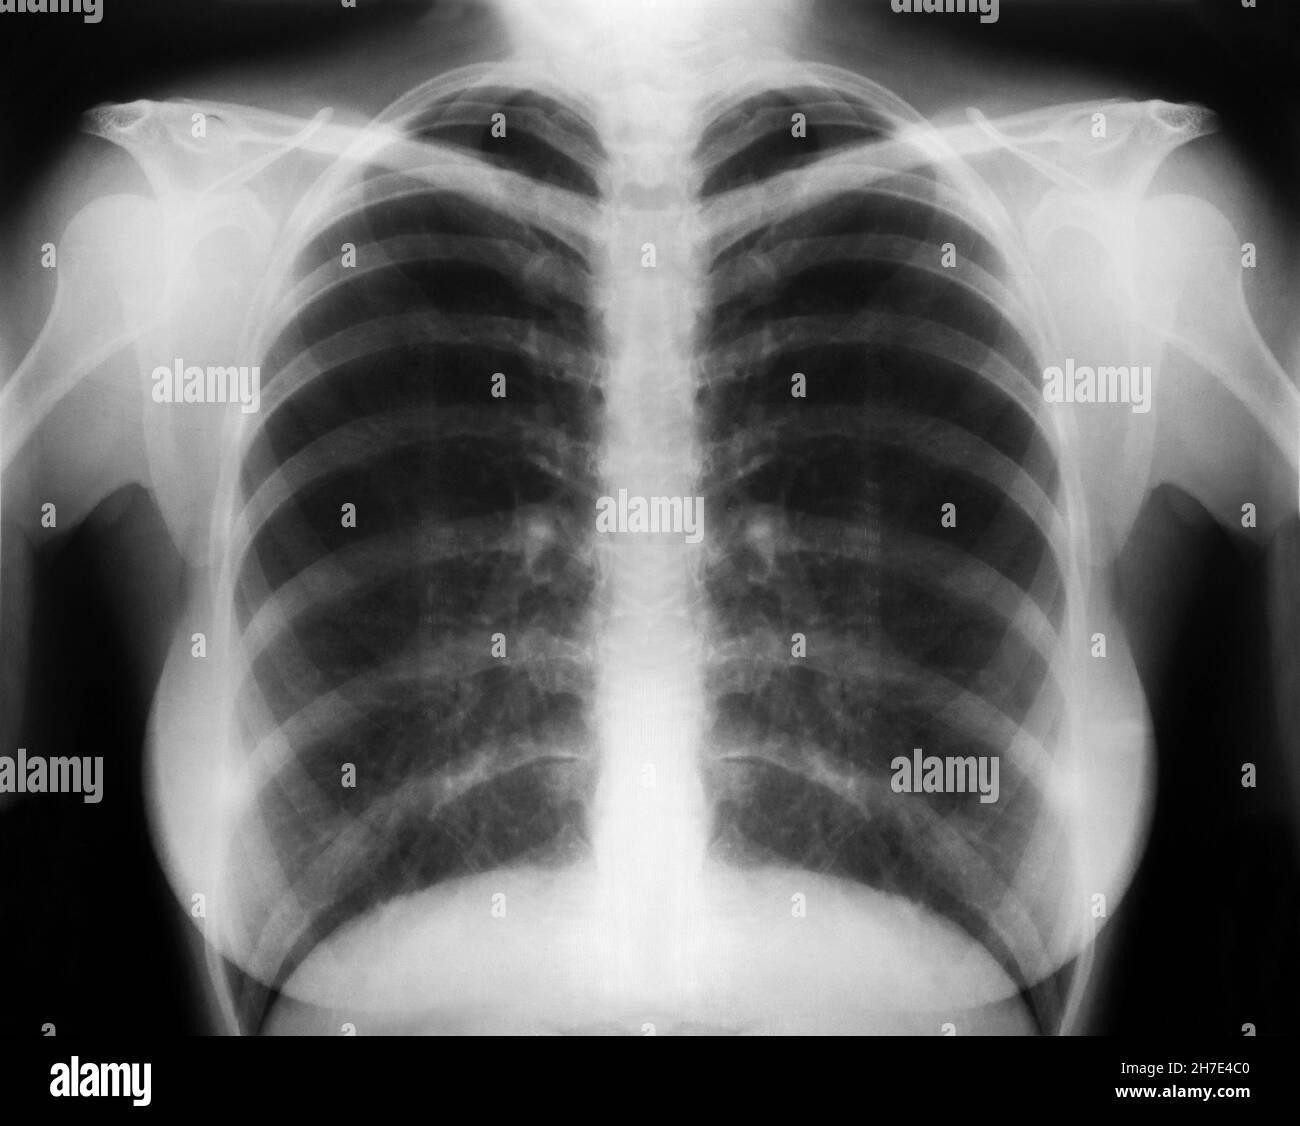

Asthma Chest X Ray Radiopaedia . Suspected pneumomediastinum, pneumothorax or surgical. — although bronchial thickening, hyperinflation, and focal atelectasis suggest asthma when they are present, chest radiographs obtained. Clinically, traditional chest radiography and computed tomography (ct) continue to play a key role in the. Chest radiographic findings in asthmatic patients are not entirely specific but, when present, include bronchial wall thickening and lung hyperinflation. A history of respiratory symptoms such as wheeze, shortness of breath, chest tightness and cough that vary over time. it is defined by two main features 1:

— although bronchial thickening, hyperinflation, and focal atelectasis suggest asthma when they are present, chest radiographs obtained. Suspected pneumomediastinum, pneumothorax or surgical. A history of respiratory symptoms such as wheeze, shortness of breath, chest tightness and cough that vary over time. it is defined by two main features 1: Chest radiographic findings in asthmatic patients are not entirely specific but, when present, include bronchial wall thickening and lung hyperinflation. Clinically, traditional chest radiography and computed tomography (ct) continue to play a key role in the.

Asthma Chest X Ray Radiopaedia Clinically, traditional chest radiography and computed tomography (ct) continue to play a key role in the. it is defined by two main features 1: Suspected pneumomediastinum, pneumothorax or surgical. — although bronchial thickening, hyperinflation, and focal atelectasis suggest asthma when they are present, chest radiographs obtained. Clinically, traditional chest radiography and computed tomography (ct) continue to play a key role in the. A history of respiratory symptoms such as wheeze, shortness of breath, chest tightness and cough that vary over time. Chest radiographic findings in asthmatic patients are not entirely specific but, when present, include bronchial wall thickening and lung hyperinflation.